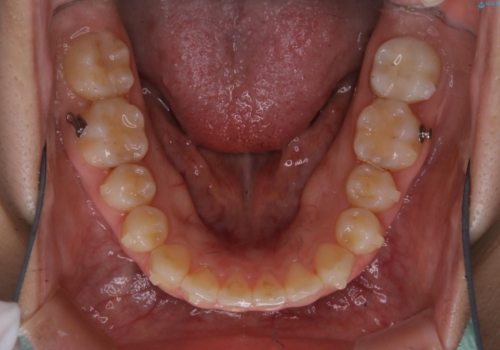

- 前歯が捻転していることを主訴に来院された方です。元々は部分矯正をご希望されていましたが、噛み合わせ等総合的に治療していくためインビザラインにて全顎的に治療を行うこととしました。

元々は上の前歯部の捻転のみの治療をご希望されていましたが、下の前歯もがたつきがあることや噛み合わせがかなり深いことを説明しました。後戻りのリスクを抑えるために全顎的な治療をご提案しました。

捻転していた上顎前歯部の仕上がりにこだわり、何度か修正を行ったため、満足のいく仕上がりになったと大変喜んでいただけました。